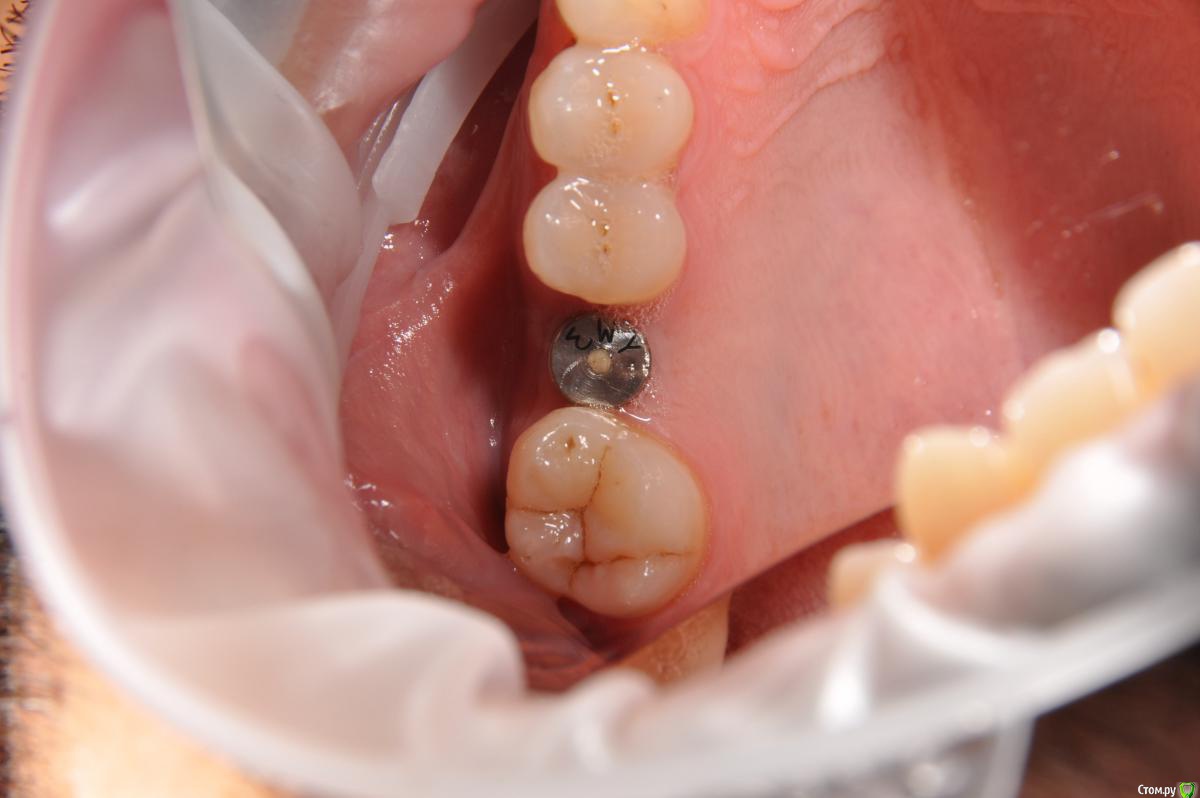

kamranchick Опубликовано 12 сентября, 2018 Автор Поделиться Опубликовано 12 сентября, 2018 Вот) Ссылка на комментарий

Евгений Ходыкин Опубликовано 12 сентября, 2018 Поделиться Опубликовано 12 сентября, 2018 Нуу...в общем... сам всё понимаешь))) Ссылка на комментарий

kamranchick Опубликовано 12 сентября, 2018 Автор Поделиться Опубликовано 12 сентября, 2018 Нуу...в общем... сам всё понимаешь))) что лучше ходить с формиком?)) Ссылка на комментарий